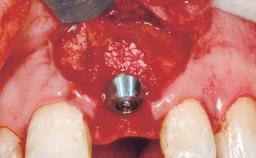

A 30-year-old female patient was referred to the office for the treatment of tooth 11. Her chief concern at the initial visit was to inquire, “Why is my tooth pink?” Upon clinical examination, it was determined that tooth 11 had a previous history of trauma and that the clinical crown had become noticeably pink in color as a result of internal resorption. This diagnosis was confirmed radiographically, indicating a large radiolucency involving the central and distal portions of the clinical crown. It was determined that restoration of this tooth was not possible, and that extraction was indicated. The presence of a mid-line diastema, which the patient wanted to reproduce, directed the treatment plan for tooth replacement utilizing a dental implant.

Placement Protocol Immediate implant placement

Socket Morphology Single-root socket

Socket Integrity Sufficient, with intact bone walls

Bone Volume Sufficient, with intact walls